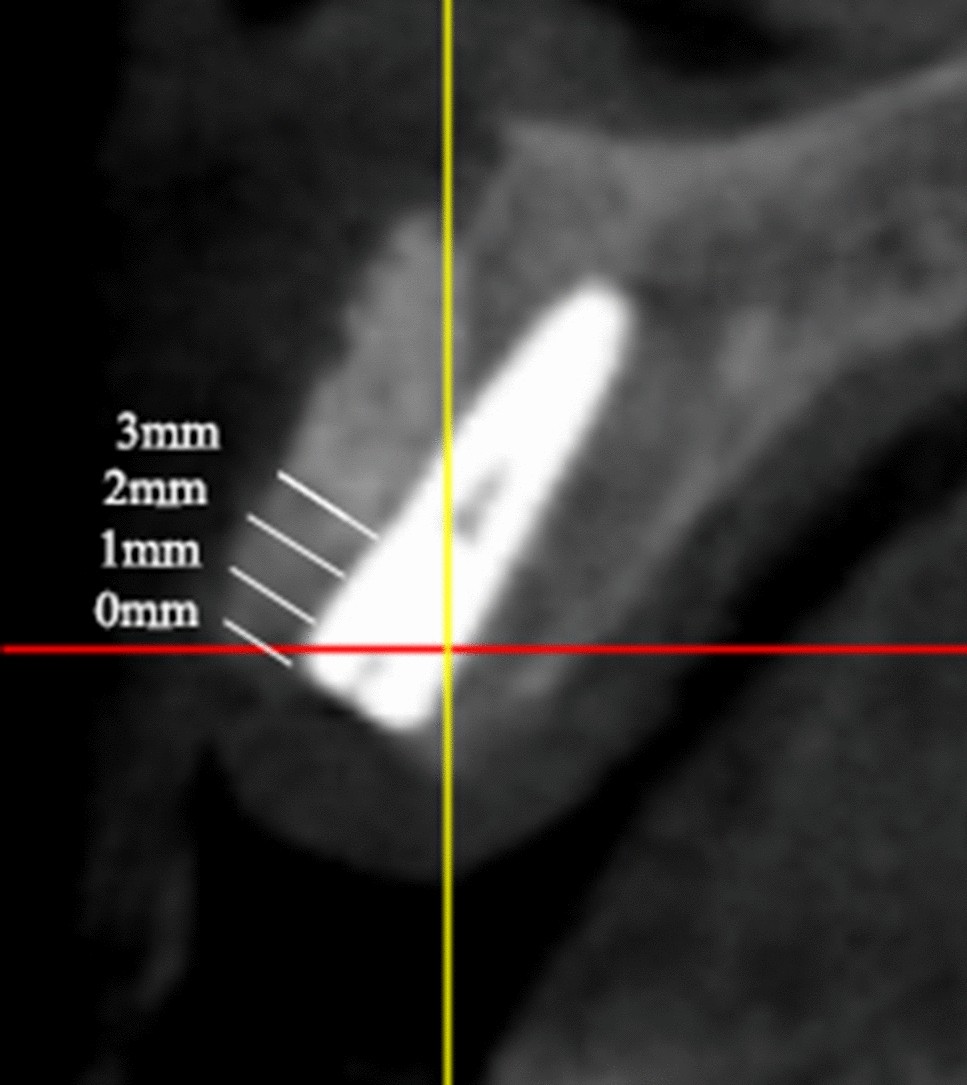

Figure 3

Measurement of bone widths at all four different levels (below the implant neck platform to 0 mm, 1 mm, 2 mm, and 3 mm).